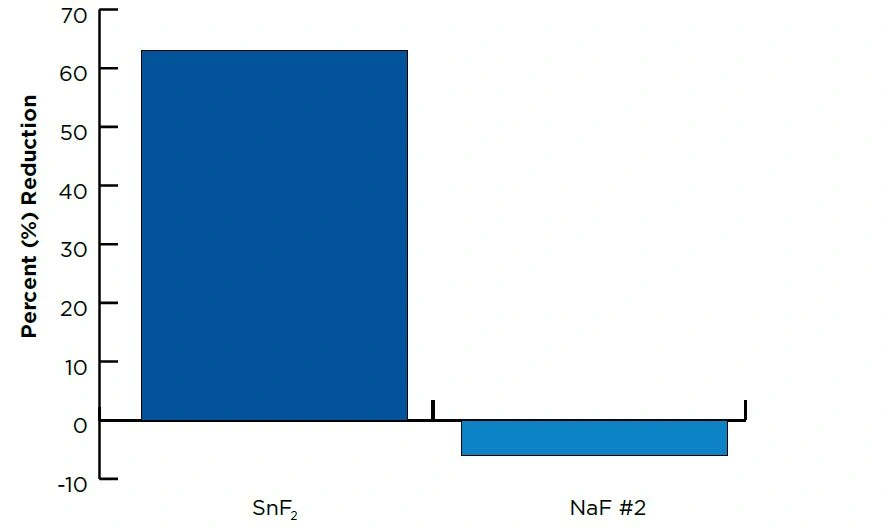

The product with RDA~150 provided significant (P=0.05, ANOVA) protection against damage (8.0μm of surface loss), with lower RDA products (RDA~50 or 100) showing no significant differences between them in their ability to protect enamel against damage (27.3 and 25.4μm of surface loss, respectively). See Table and Figure.

It is important to note the active F species in the RDA~150 formulation was SnF2. SnF2 provides significant protection against erosive acid damage by forming a protective barrier layer on the enamel surface, protecting against external challenges.

Figure Average % Reduction in Total Mineral Loss*

*(vs. NaF product)